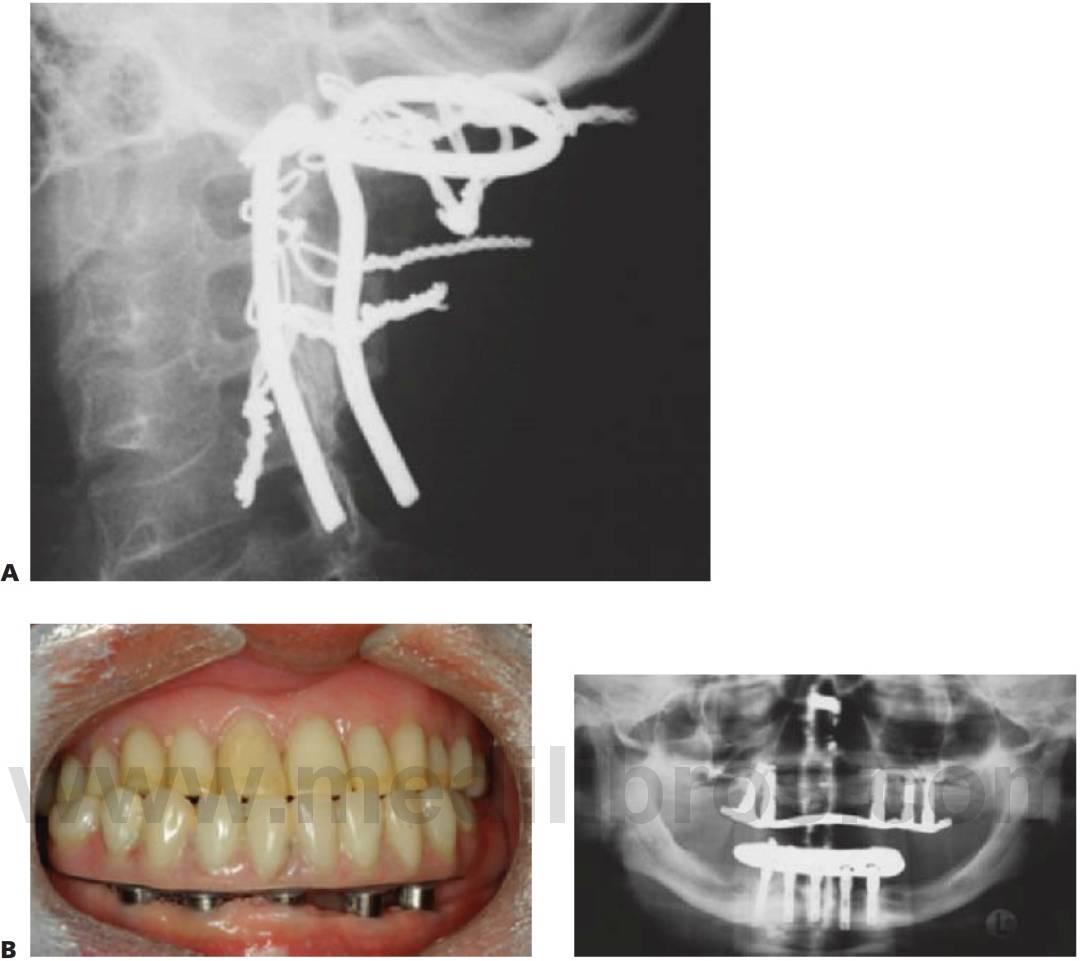

Implantes osteointegrados en niños

Existe una polémica considerable acerca del momento más adecuado para la colocación de implantes osteointegrados en niños pequeños. Hasta la fecha se han publicado pocos trabajos sobre la implantación temprana y sus consecuencias a largo plazo. En general, se considera que los implantes actúan de forma muy parecida a los dientes anquilosados y no se mueven de forma oclusal al crecimiento del hueso alrededor de los dientes naturales adyacentes. Una reciente investigación en animales han confirmado que la mayoría de las fijaciones se osteointegran en el maxilar y la mandíbula en crecimiento, aunque los datos derivados de esta investigación no evidencian que las fijaciones se comporten igual que los dientes naturales durante el desarrollo. En la mandíbula los implantes se desplazan en sentido lingual a los dientes naturales, y en el maxilar superior se desplazan en sentido palatino y superior a los dientes adyacentes y no siguen el crecimiento anteroinferior de este hueso. Este último detalle tiene gran importancia cuando se plantea la posibilidad de colocar implantes en la parte anterior del maxilar superior. Además, la colocación de fijaciones retrasaba el crecimiento alveolar a nivel local y alteraba la ruta de erupción de los gérmenes dentarios colocados distalmente. En la mayoría de los casos no se deben colocar implantes a niños durante el período de crecimiento, si bien conviene señalar que aquellos niños que presentan trastornos como displasia ectodérmica no desarrollan el hueso alveolar en las zonas de ausencia congénita de dientes; por tanto, se considera apropiado colocar implantes en estos niños mucho antes que en los que tienen unos alveolos normales, sobre todo cuando se presentan muchas agenesias dentales. Investigaciones recientes indican que, en casos de anodoncia, la mejor zona para colocar los implantes es la región canina mandibular, y el momento a los 8-10 años de edad (siguiendo el período de crecimiento transversal mandibular máximo) para facilitar la fabricación de la prótesis inferior.